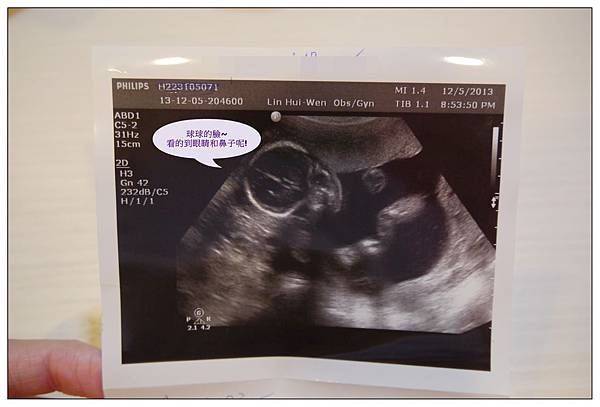

下面這張超可愛的~~~看的到球球的兩個眼眶~~~~